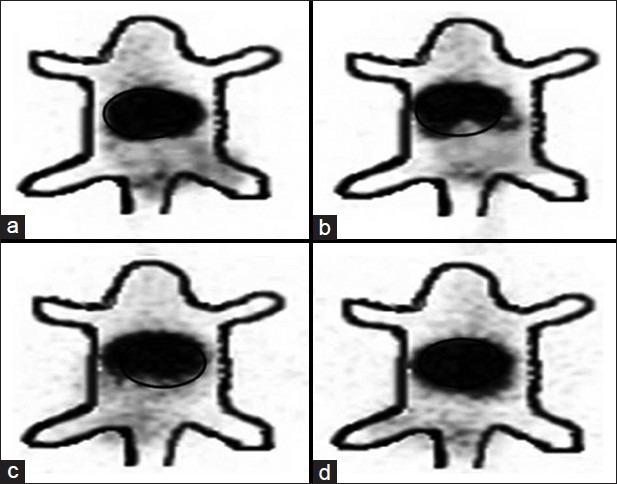

Mean size of the etoposide loaded PLGA nanoparticles was found to be 105.1 nm. The concentration of both free etoposide and nanoparticles increased with time and showed higher tumor concentrations of both free etoposide and nanoparticles increased with time and showed higher retention, indicating their applicability in effective and prolonged tumor therapy. Nuclear scintigraphic images confirm the presence of labeled complexes at the site of tumor for 24 h at higher concentration than in the normal muscles.

负载依托泊苷的PLGA纳米颗粒的平均粒径为105.1 nm。游离依托泊苷和纳米颗粒的浓度均随时间增加,且游离依托泊苷和纳米颗粒在肿瘤中的浓度均随时间增加并显示出更高的滞留率,表明它们在有效的长期肿瘤治疗中的适用性。核闪烁图像证实标记复合物在肿瘤部位存在24小时,其浓度高于正常肌肉。